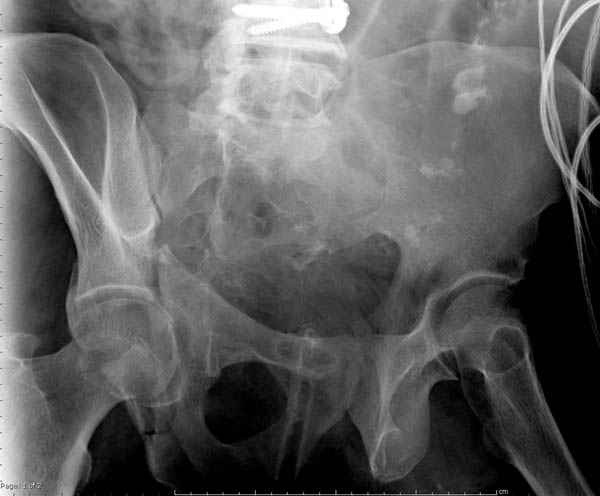

По возможности вышлите снимки, сканы таза до

реконструкции, интраоперационные.

По снимку создается впечатление о высоком поперечном переломе, задней колонны, стенки; почему не пользовались *magic screw*?

Снимки здесь....